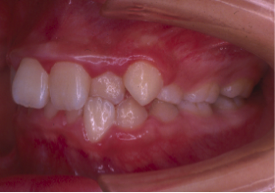

治療前

治療後

矯正治療と外科手術を併用して行った患者さんです。

「早い治療計画」での依頼のため、歯を抜かずに矯正治療を10ヶ月行い手術という事になりました。

その後6ヶ月の術後矯正にて終了となりました。

手術も含めて早期治療が目的の患者さんでしたので満足されてよかったです。